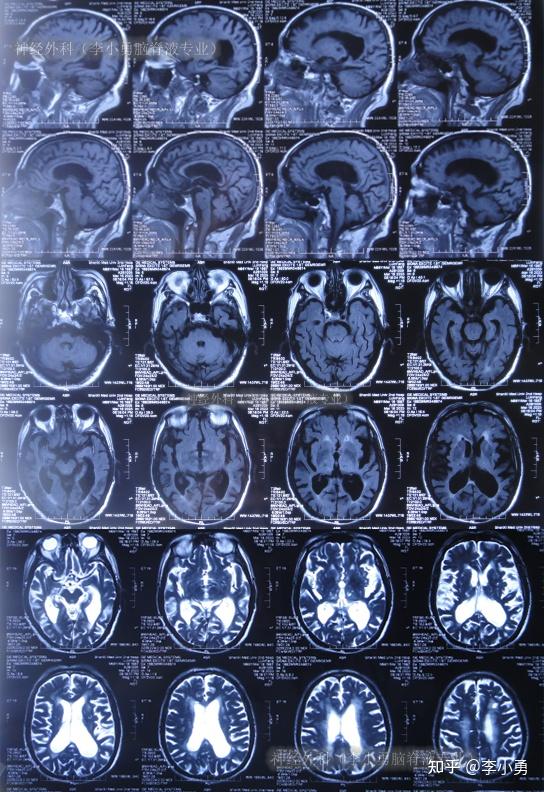

并发脑萎缩的老年正常压力脑积水步态不稳走路前冲不能控制